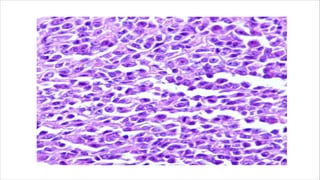

Epithelioid angiosarcoma

• Rare variant of angiosarcoma

• Composed of predominantly endothelial cells that have

epithelioid features.

• Occurs frequently in older adults

• Peak incidence in seventh decade of life.

• Seen in deep soft tissue of extremities and are commonly

intramuscular.

Microscopy

• Large, mildly to moderately pleomorphic , round to polygonal

epithelioid cells with eosinophilic cytoplasm, vesicular nuclei

containing prominent nucleoli.

• Arranged into solid sheets and nests which may resemble

malignant epithelial tumours or melanomas.

• Anastomosing vascular spaces indicating of rudimentary vaso

formative potential.

• Sheeted areas contain scant stroma.

• Stroma may be more prominent loosely myxomatous or

desmoplastic.

Immunochemistry

• Hybrid nature of tumour cells which express epithelial or

mesenchymal cells markers.

• Mitoses and areas of necrosis are seen.